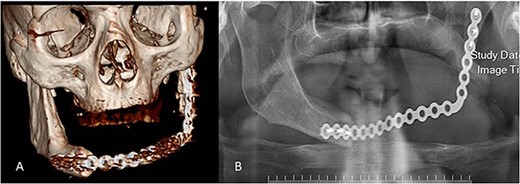

No evidence of recurrence was observed after 2 years (Fig. 8).

Postoperative radiographs. (A) 3D view of the reconstruction plate. (B) Panoramic view of the reconstruction plate after 24 months.